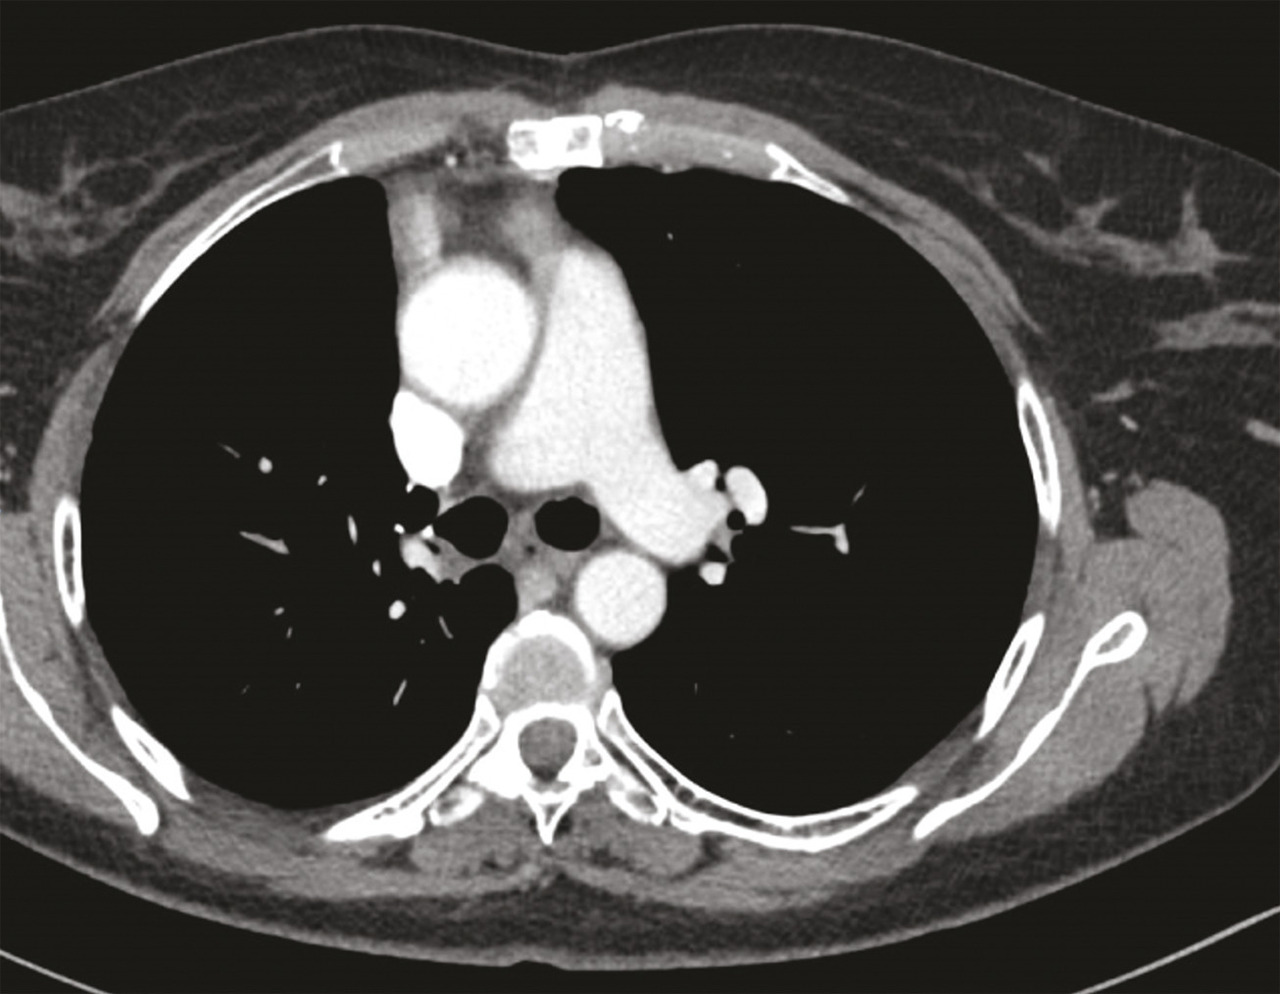

Une imagerie par résonance magnétique (IRM) du crâne réalisée 15 jours après le début des symptômes n’a pas montré d’anomalie. Toutefois, leur persistance et leur aggravation ont fait demander à son médecin traitant un dosage des anticorps antirécepteurs à l’acétylcholine, qui s’est révélé positif, conduisant au diagnostic de myasthénie. Des anticholinestérasiques ont alors été prescrits en première intention, permettant d’améliorer transitoirement les symptômes musculaires. Leur effet est de prolonger l’action de l’acétylcholine au niveau de la membrane post-synaptique par blocage réversible de l’acétylcholinestérase (deux médicaments sont disponibles : la pyridostigmine et l’ambénomium). Dans le cadre du bilan de cette myasthénie, une tomodensitométrie thoracique est pratiquée, qui met en évidence une masse médiastinale antérieure, volumineuse et polylobée évoquant une tumeur thymique (fig. 1).1